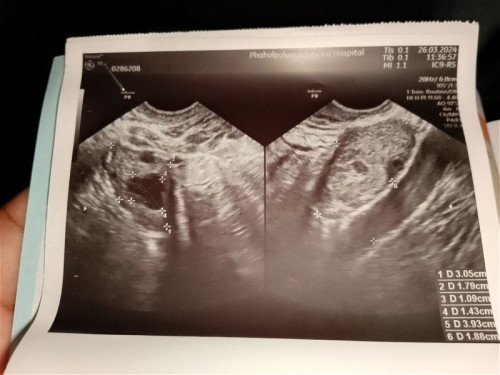

ตั้งครรภ์ได้ 5 สัปดาห์

ไปฝากท้องมาแล้วไปอัลตร้าซาวด์แล้วไม่พบถุงตั้งครรภ์หมอนัดอีก 2 วันเพื่อไปตรวจหาค่าฮอร์โมนแบบนี้มีเสี่ยงที่จะเป็นท้องนอกมดลูกไหมคะ (ตรวจค่าฮอร์โมนอันเก่าได้ 2,000 กว่า)